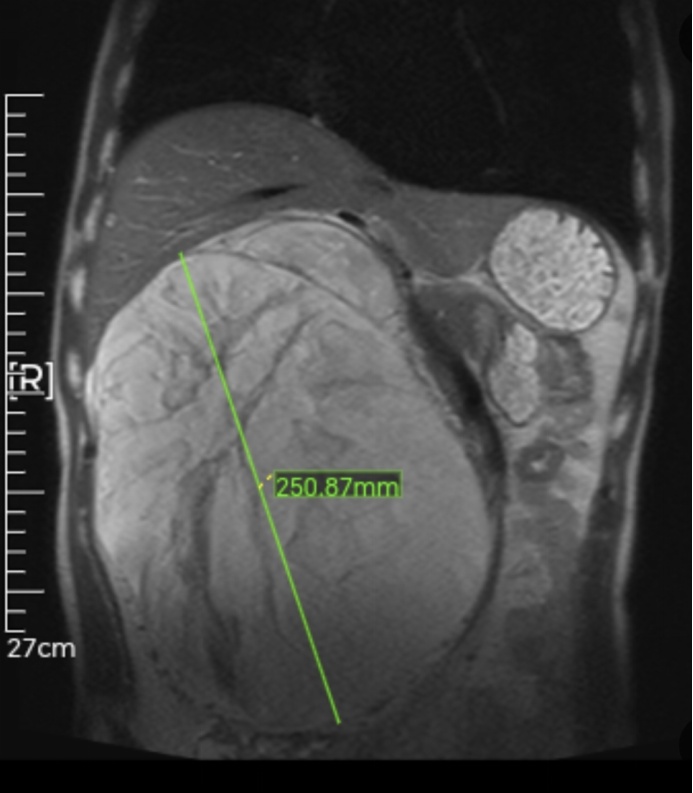

泌尿外科陆国梁副主任医师接诊后深知,这将是一场硬仗。影像显示:张先生右侧腹腔内,长出了一个直径约25cm的巨大肿瘤。它几乎占据了整个腹腔,体积堪比一只篮球。

但这还不是最可怕的。真正让医生们捏一把汗的是肿瘤的“邻居”关系。这颗巨大的“肉球”不仅侵犯了张先生的右侧肾脏,还极其霸道地将肝脏向上推移,十二指肠、胰腺等重要器官全部推压到了左侧腹腔。原本管状的下腔静脉(人体最大的静脉血管),被硬生生压成了扁平的直线状。更危险的是,肿瘤表面血管怒张,血供极其丰富。